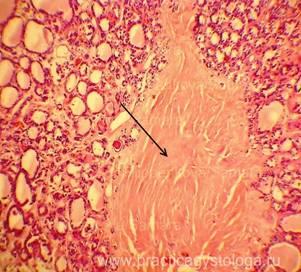

Микропрепараты: Лимфогранулематоз и Нодулярный Склероз